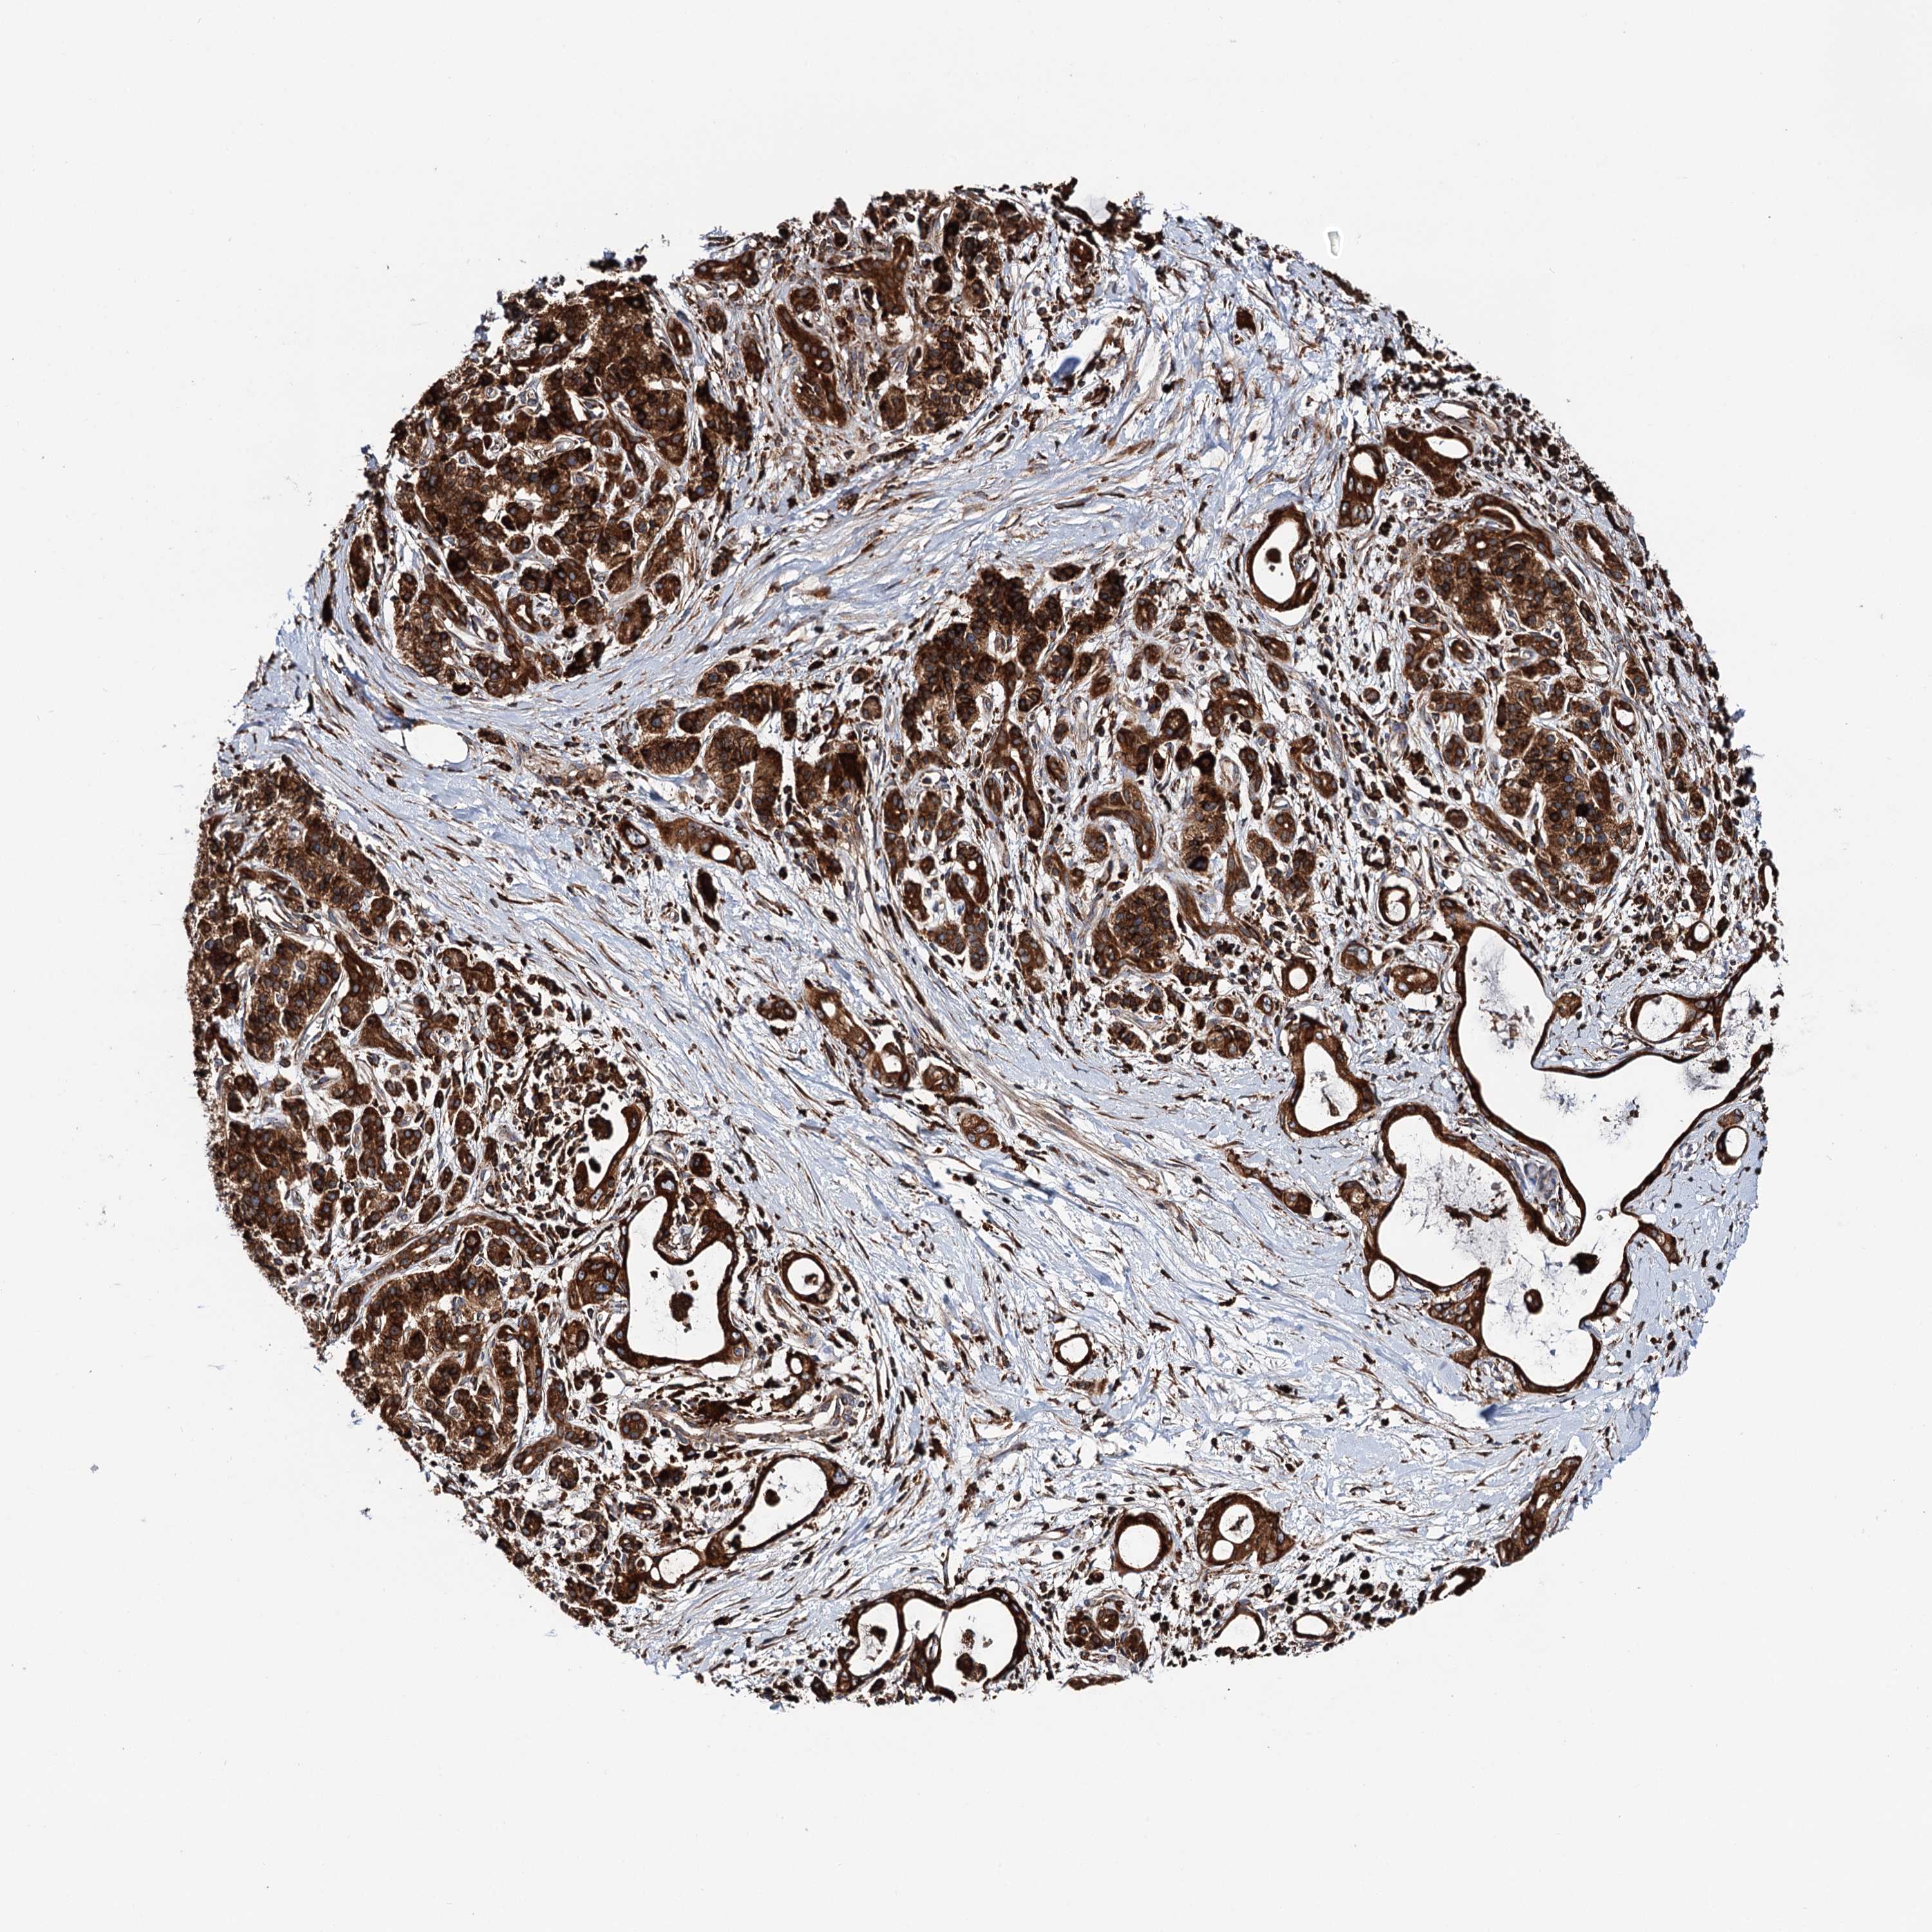

PANCREATIC CANCER - Protein expressioni

A mouse-over function shows sample information and annotation data. Click on an image to view it in a full screen mode. Samples can be filtered based on level of antibody staining by selecting one or several of the following categories: high, medium, low and not detected. The assay and annotation is described here.

Note that samples used for immunohistochemistry by the Human Protein Atlas do not correspond to samples in the TCGA dataset.

Antibody stainingi

Antibody staining in the annotated cell types in the current human tissue is reported as not detected, low, medium, or high, based on conventional immunohistochemistry profiling in selected tissues. This score is based on the combination of the staining intensity and fraction of stained cells.

Each image is clickable and will lead to virtual microscopy that enables deeper exploration of all samples and also displays staining intensity scores, fraction scores and subcellular localization as well as patient and tissue information for each sample.

Antibody HPA039363

Antibody HPA039456

Staining

High

Medium

Low

Not detected

Intensity

Strong

Moderate

Weak

Negative

Quantity

>75%

75%-25%

<25%

None

Location

Nuclear

Cytoplasmic/membranous

Cytoplasmic/membranous,nuclear

Adenocarcinoma, NOS